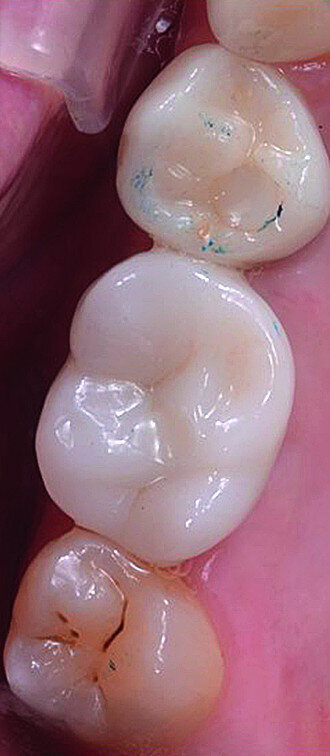

In March 2018, four months after the surgery, the prosthetic phase was started. An impression was taken with an intraoral scanner (CS 3600, Carestream Dental) using scan bodies for an impression at the implant head (MegaGen; Figs. 11a & b). The information was sent to the Anatomic Lab, where a crown was designed using a CAD programme. After the design of the crown had been finished, the information was sent to a milling machine (Amann Girrbach) and the crown was milled (Fig. 12). One week after the preparation, the definitive crown in monolithic zirconia was attached and the occlusion tested using T-Scan technology (Tekscan; Figs. 13a–c & 14).